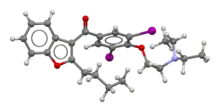

| Formula | C25H29I2NO3 |

| Molar mass | 645.320 g·mol−1 |

| 3D model (JSmol) | |

Amiodarone may be an acronym for its IUPAC name (2-butyl-1-benzofuran-3-yl)-[4-[2-(diethylamino)ethoxy]-3,5-diiodophenyl]methanone,[62] where ar is a placeholder for phenyl. This is partially supported by dronedarone which is noniodinated benzofuran derivative of amiodarone, where the arylmethanone is conserved.